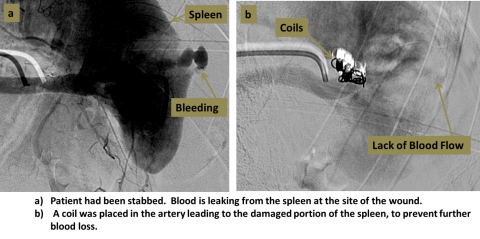

Embolization procedures allow blockage of blood vessels without invasive surgery. Embolization can be used to stop arterial bleeding, and can also be used to block blood vessels for other reasons, such as to treat tumors, shrink vascular malformations, or re-direct flow.

An interventional radiologist accesses the femoral artery at the groin. Small catheters and wires are used to navigate into the chosen artery, confirmed with angiography. An occluding substance can then be injected, or small coils can be placed into the artery to block the vessel.